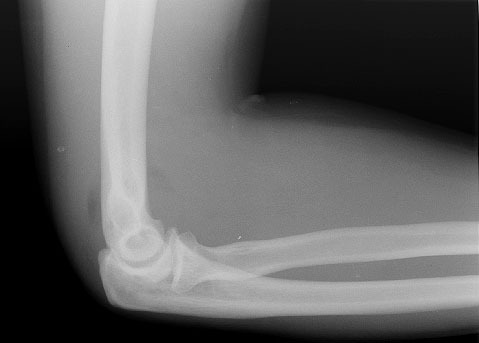

I hate having a broken elbow.

Bunny, I fractured my radial head.

It's a minor fracture (just a crack, really), so the doctor said 3-6 weeks, so in my mind, I can take my splint off in two weeks. I guess I should play it by ear.